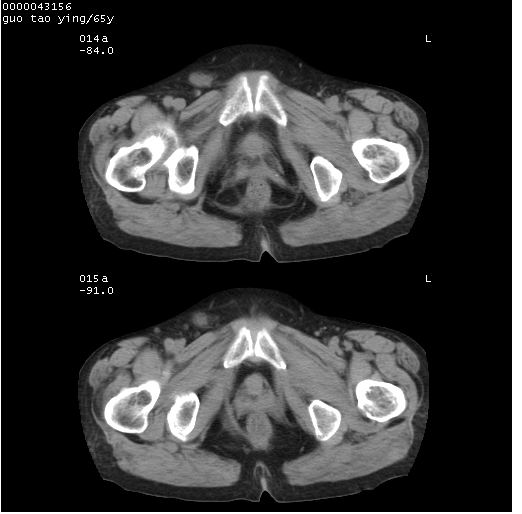

以下是引用黑白光影在2008-1-30 13:22:00的发言:[br]支持左耻骨骨折。[br]未见骶骨骨质明确破坏改变。[br]经楼主提示(勿局限于外伤)。考虑为右侧腹股沟直疝。[br][br][br][br]